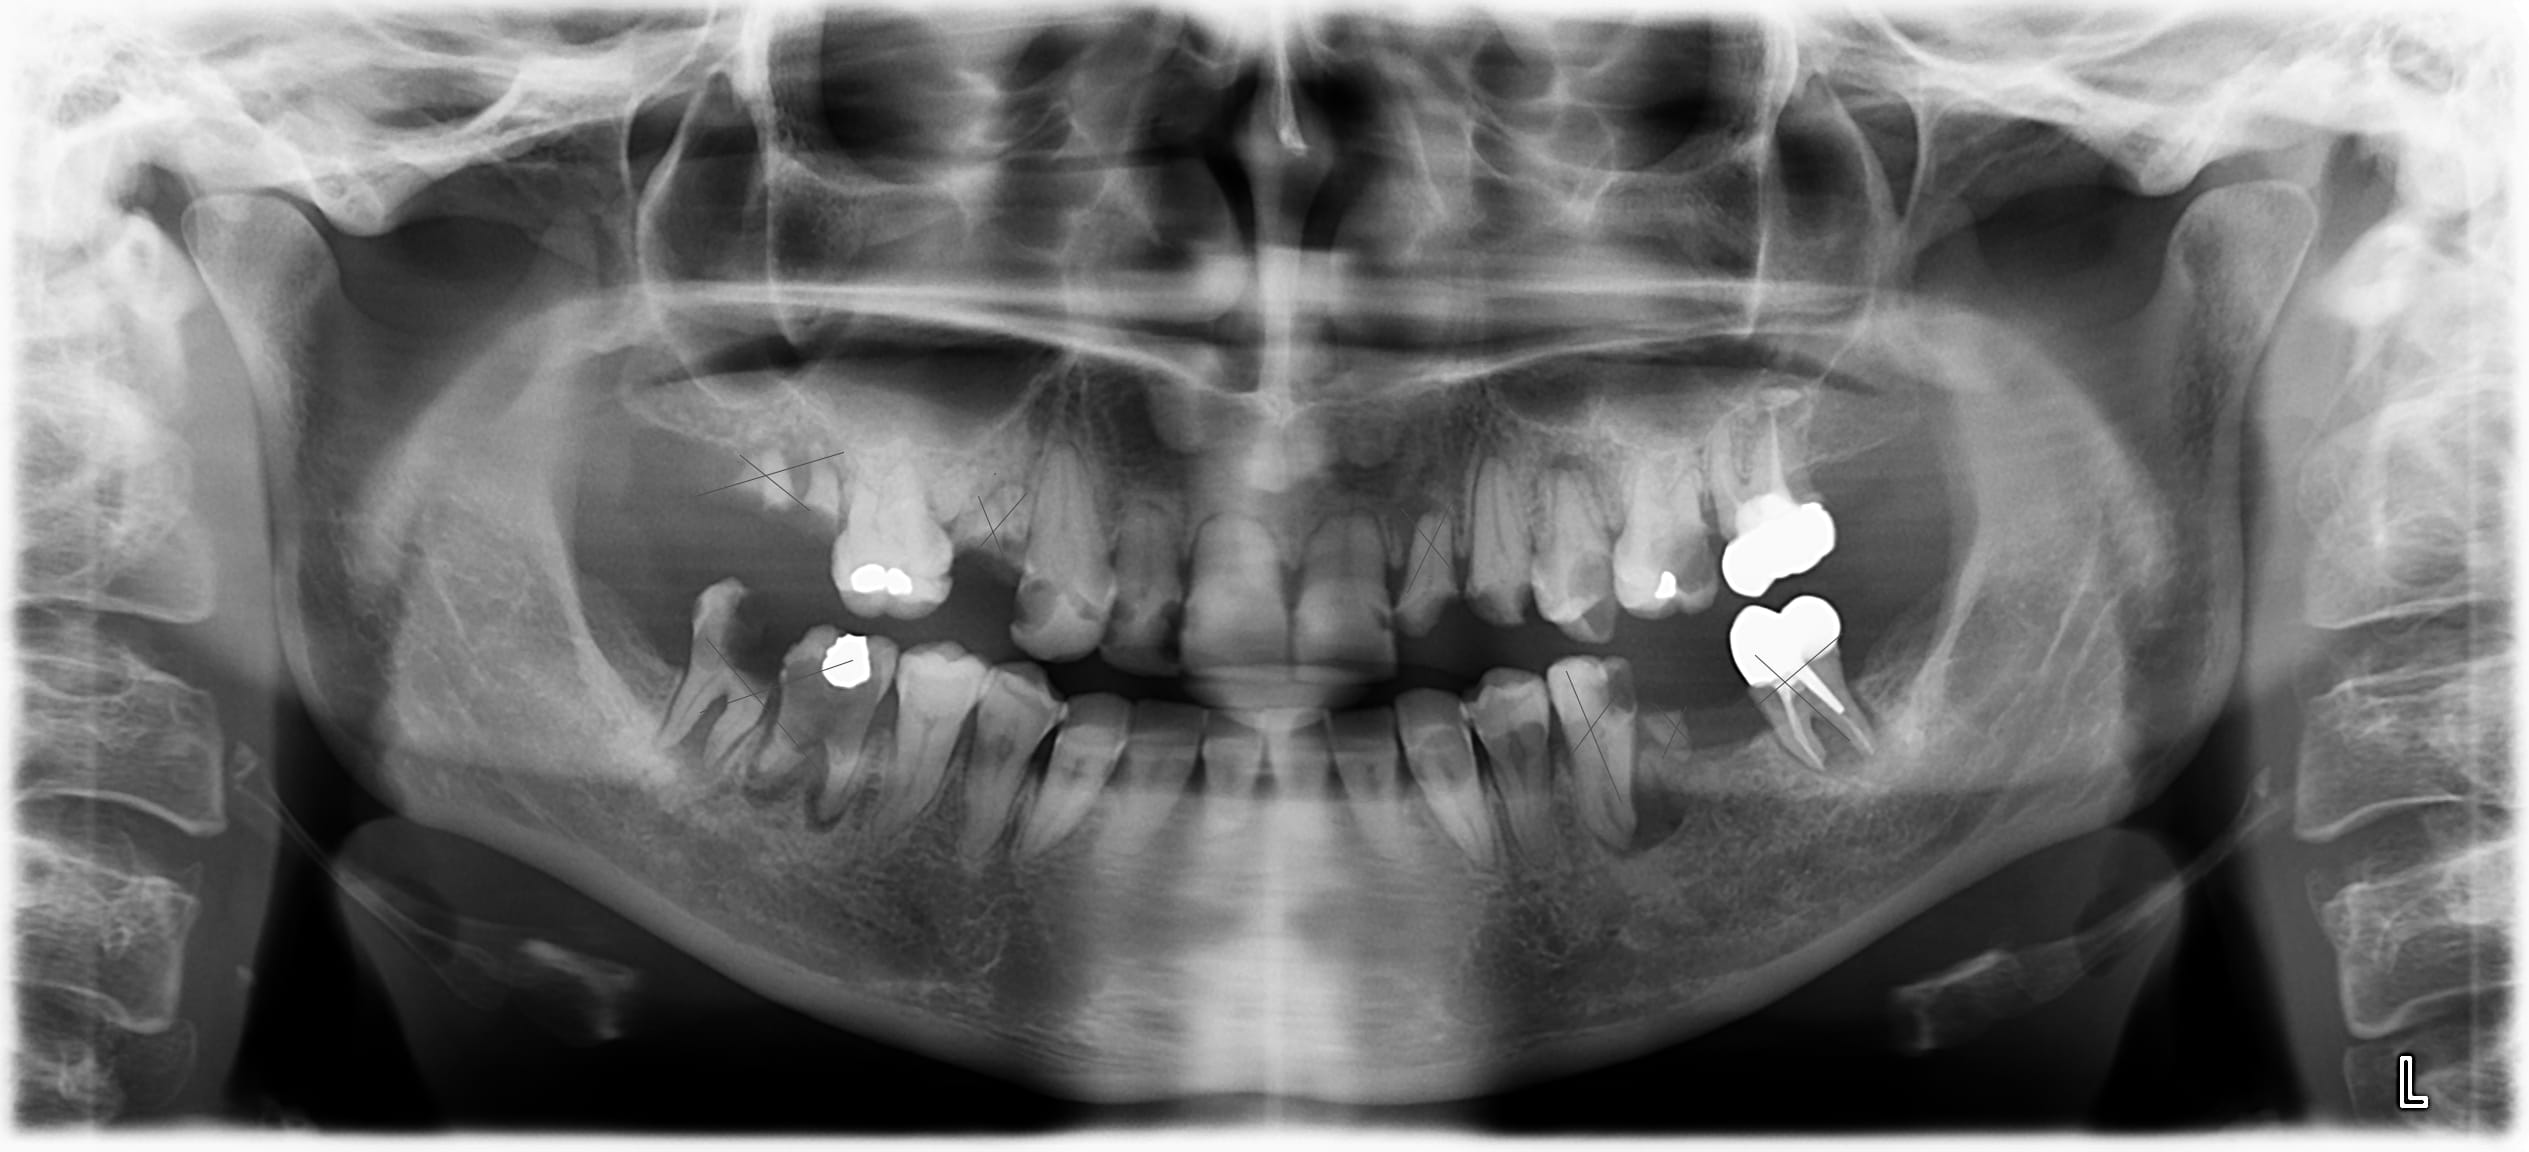

J'ai reçu cette patiente (35 ans) en consultation pour des douleurs modérées.

A la mandibule je vais enlever 47/46/37/36 et 35 mobile+. Le reste en bas sont des caries du collet importantes mais rattrapables encore. Et après appareil en bas.

Au maxillaire je vais enlever 17/15 et 22 sur.

C'est pour le reste que je bloque... La 12/23/25/26 sont vraiment très abîmées et nécessiterait d’être dévitalisée puis couronnées. Sauf que au vu de la longueur des racines j'ai peur que cela ne soit pas possible, tout comme s'appuyer sur ces dents pour mettre en place un appareil en haut...

On manque de pas mal d'éléments pour affiner, mais au vu de la pano je dirais ça:

Ici je vire tout en haut.

En bas tu peux en garder quelques unes, mais faut des rétro.